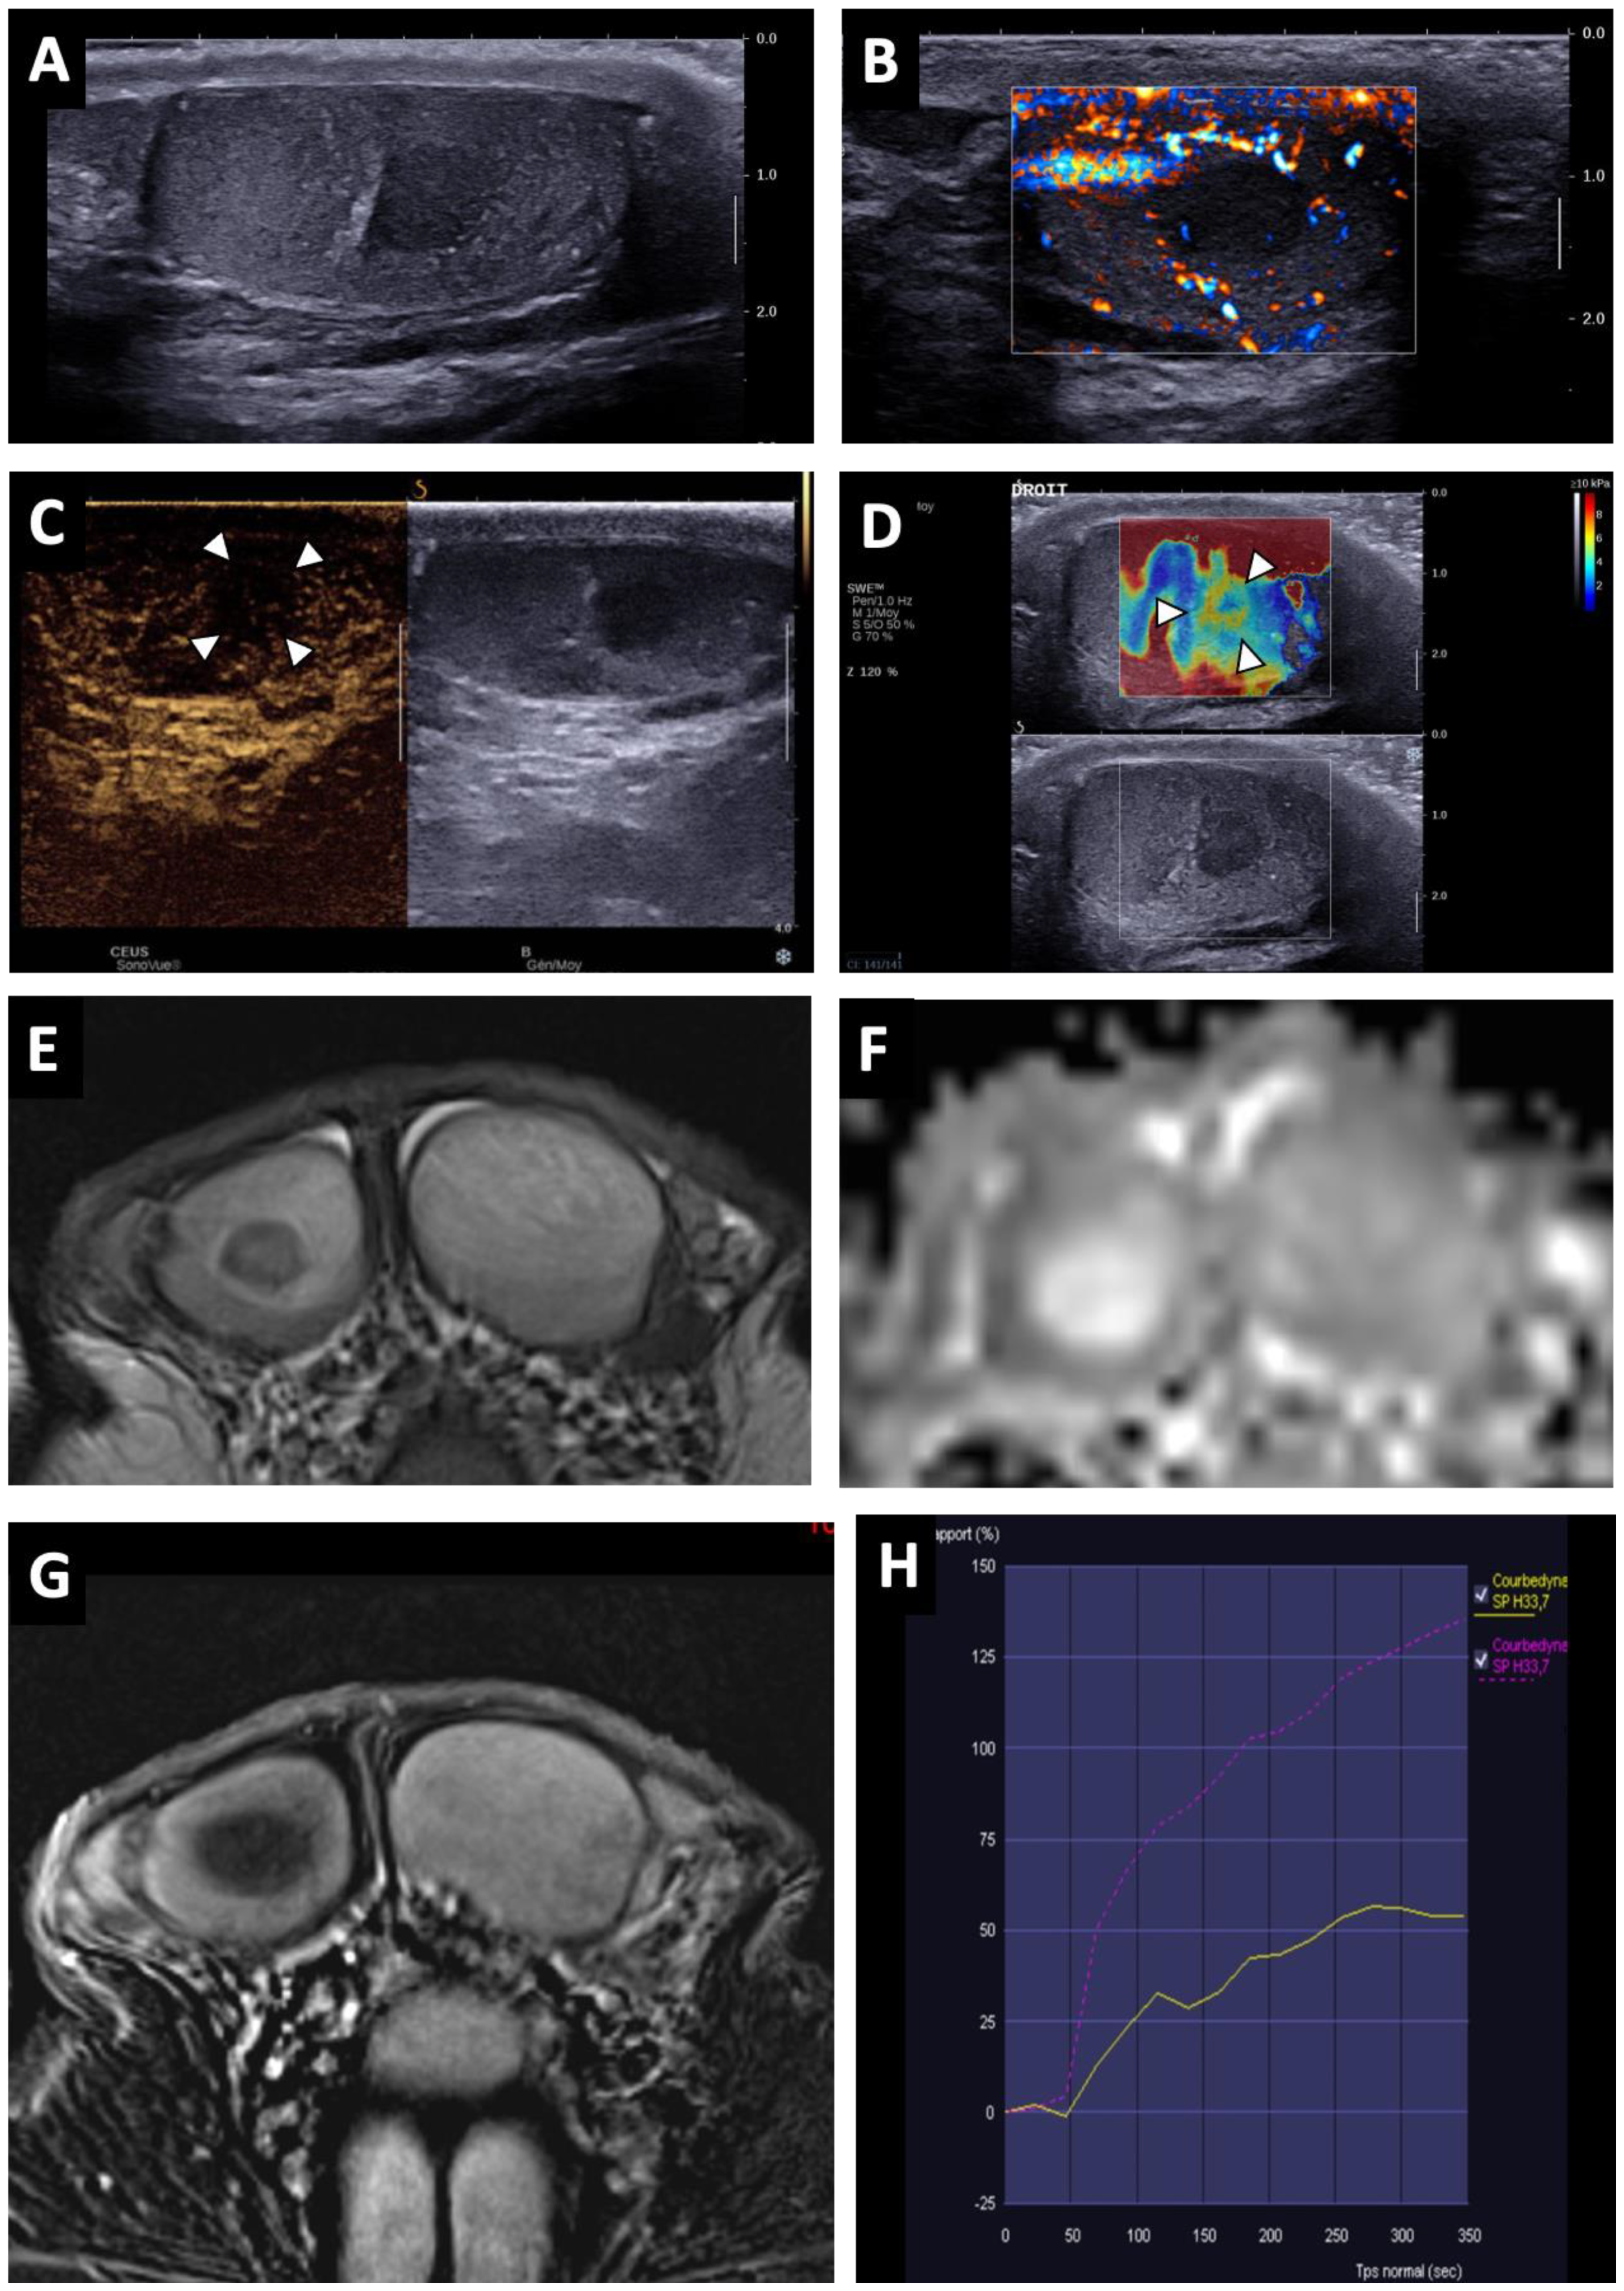

3.2.1. Conventional US Findings

3.2.2. MRI Findings

| Lesion pattern | ||||

| - Nodular area | 22 (84.6) | 11 (100) | 10 (90.9) | 44 (91.7) |

| - ill-delineated | 26 (100) | 11 (100) | 11 (100) | 48 (100) |

| Echogenicity | ||||

| - Hypoechoic | 25 (100) | 11 (100) | 11 (100) | 48 (100) |

| Vascularization | ||||

| - Hypovascular | 20 (76.9) | 11 (100) | 11 (100) | 42 (87.5) |

| - Hypovascular area with hypervascular focal nodule | 6 (23.1) | 0 | 0 | 6 (12.5) |

| Lesion shape (T2WI) | ||||

| - Round or oval nodule | 18 (81.8) | 8 (80) | 9 (100) | 34 (82.9) |

| Lesion signal | ||||

| - Hyposignal on T2WI | 22 (100) | 10 (100) | 9 (100) | 41 (100) |

| - Hyposignal on DWI | 17 (77.3) | 10 | 0 | 32 |

| - Hyposignal with focal hypersignal spot on DWI | 5 (22.7) | 0 | 0 | 5 (12.2) |

| DCE T1WI | ||||

| - Reduced enhancement matching to lesion | 3 (13.6) | 3 (30) | 3 (33.3) | 9 (22) |

| - Reduced enhancement overlapping the lesion | 13 (59.1) | 7 (70) | 6 (66.7) | 26 (63.4) |

| - Reduced enhancement overlapping the lesion with focal early and strongly enhanced nodule | 5 (22.7) | 0 | 0 | 5 (12.2) |